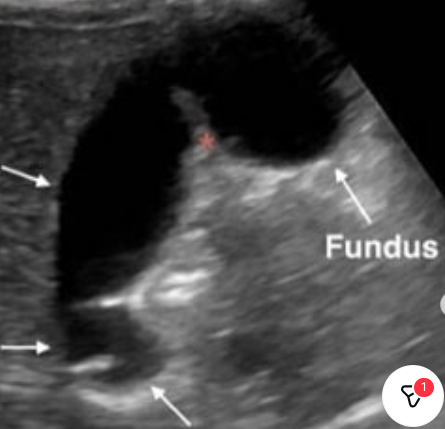

Acute cholecystitis with wall thickening, stones, and pericholecystic fluid